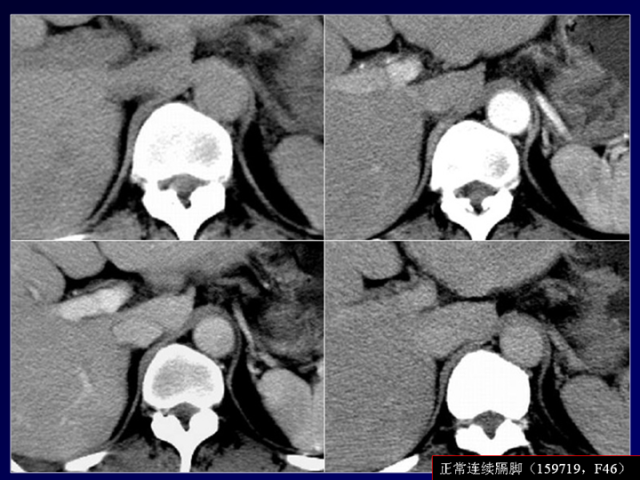

膈肌角解剖及常见变异

作者:王俭 上海长征医院